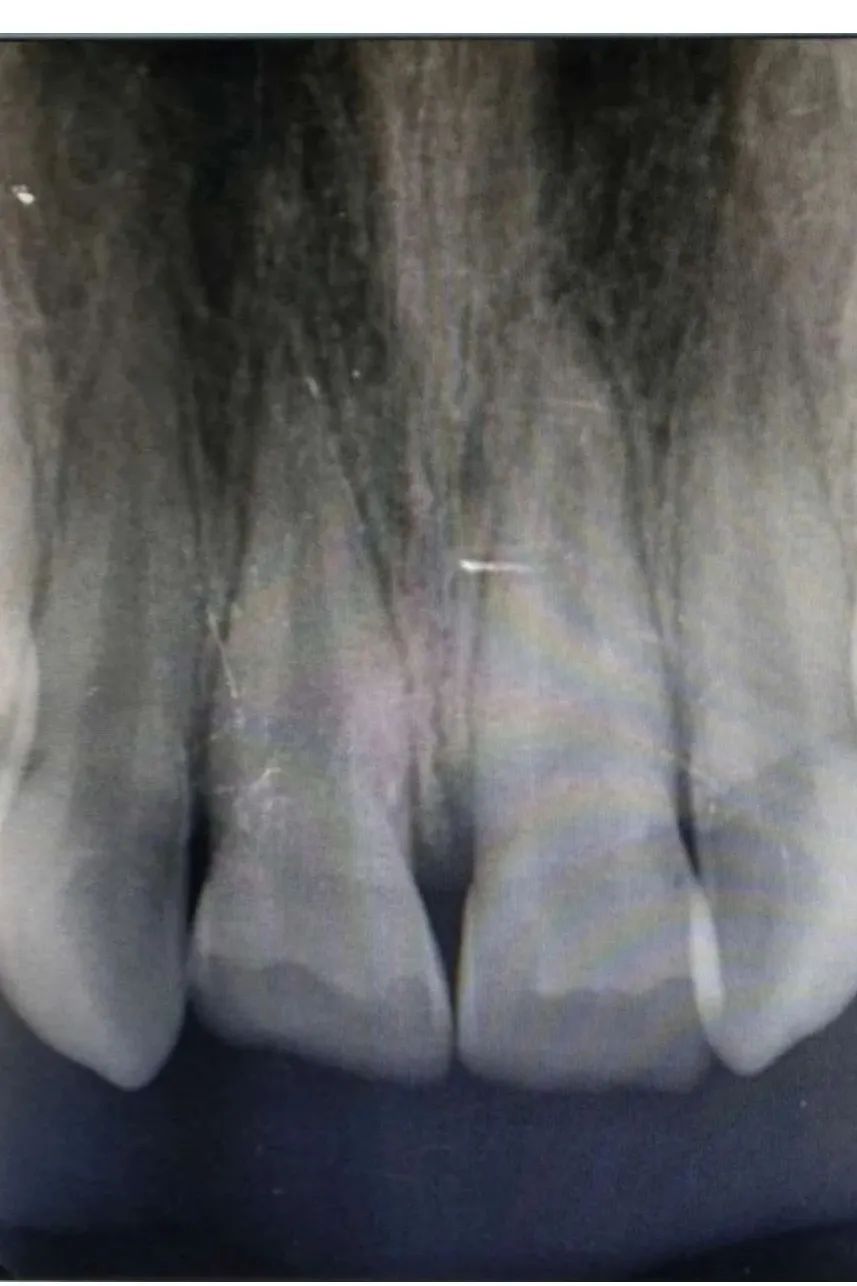

检查发现冠折露髓,两颗上门牙牙冠都缺损三分之二,牙髓暴露渗血,其中一颗有裂纹。幸运的是,虽然牙冠折断了,但拍片显示牙根没有明显折断且发育良好,可进行根管治疗,将断了的牙齿“接”回来。

儿童口腔科张晨医生在杨玉娥主任的指导下,连夜给小丽做了牙髓摘除,便于其吃饭,并于次日上午与冯娜医生一起共同完成了根管治疗和裂纹修复。经过前后数个小时的治疗,小丽摔碎的牙冠被成功地粘接回原来的位置,恢复了美丽笑容。